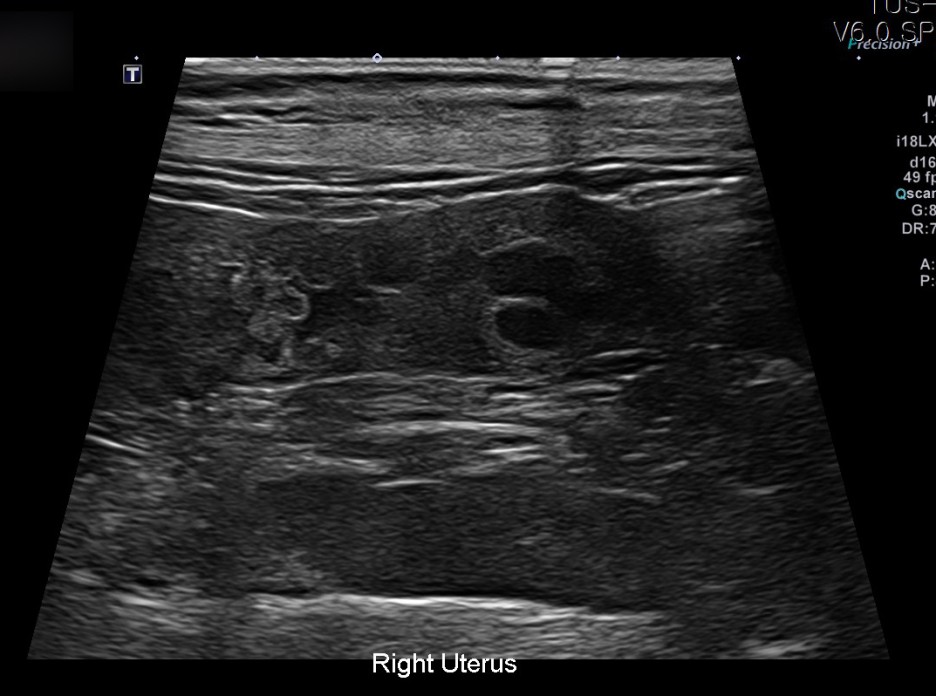

이어 진행된 초음파 검사에서는 자궁축농증으로 인해 내막이 두꺼워지고 크기가 커지는 염증성 변화가 진행되고 있었습니다.

✔US 양 자궁내막증식, 자궁각내삼출물에 의한 심한 확장소견